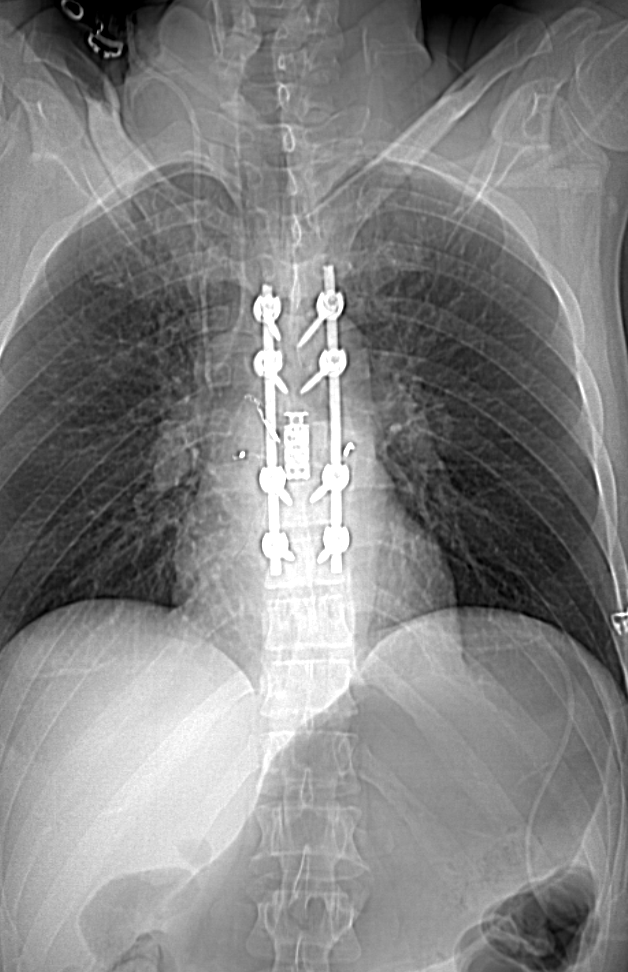

圖像顯示了用于穩(wěn)定和融合安迪·舒爾脊柱的儀器。

二天,舒爾和烏里韋醫(yī)生一起接受了7個小時的手術,切除了腫瘤,穩(wěn)定了脊柱。烏里韋醫(yī)生切除了腫瘤生長的T7椎骨的一部分,并插入了一個骨移植物和籠子將相鄰的椎骨融合在一起。為了進一步穩(wěn)定脊柱和支持骨融合,Uribe博士在T5到T9之間放置了兩根鈦棒,并用八個螺釘固定。